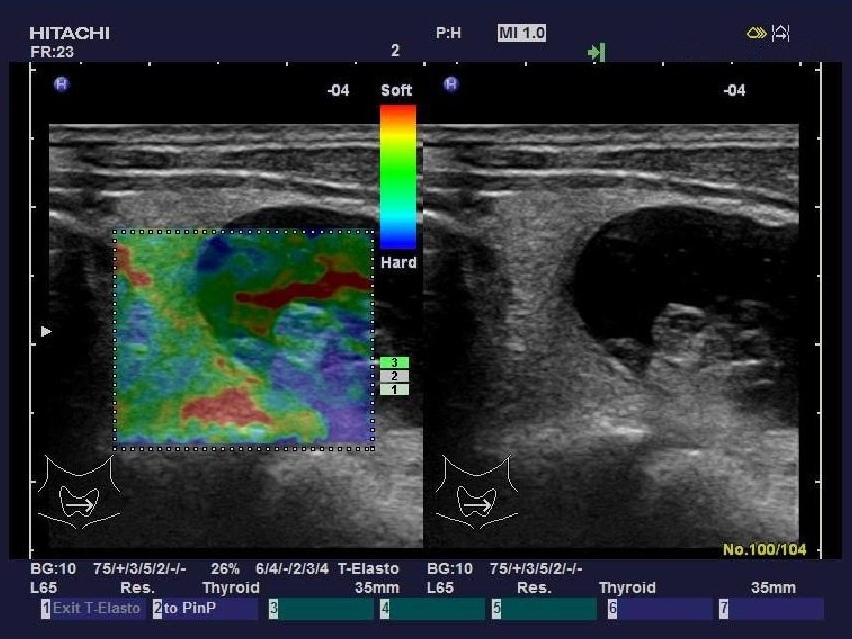

實(shí)時(shí)組織彈性成像技術(shù)

(Real-time Tissue Elastography)

“ARIETTA 70”加載了彈性成像功能,實(shí)時(shí)組織彈性成像技術(shù)是根據(jù)人體不同組織受壓后的變形差別,將其不同的組織的彈 性系數(shù)差異用不同的彩色顯示出來的新成像診斷技術(shù)。

組織彈性成像技術(shù)完全脫離了常規(guī)超聲聲阻抗成像原理,開辟了超聲診斷原理的新領(lǐng)域。將指尖的觸診高速信息化數(shù)字化,不 僅實(shí)現(xiàn)了定性分析,還具備定量分析功能。

臨床應(yīng)用領(lǐng)域:乳腺、甲狀腺、前列腺、皮膚、肝臟、子宮、卵巢、胰 腺、淋巴結(jié)、血管、直腸、睪丸、顱腦及多種術(shù)中檢查。

甲狀腺方面:如甲亢、結(jié)節(jié)性甲狀腺腫、甲狀腺腺瘤、甲狀腺癌等。